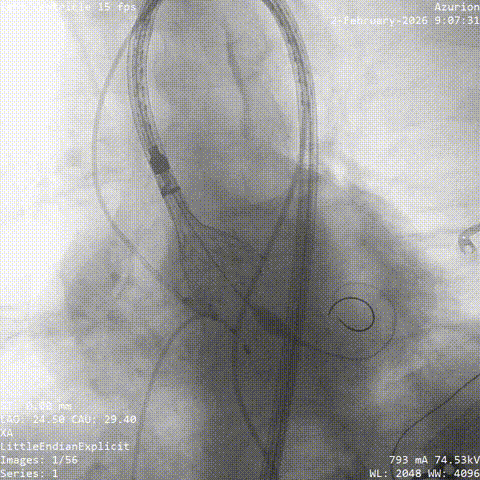

冠脉治疗后一周,张老先生整体状态平稳,进入主动脉瓣置换阶段。团队从股动脉建立通道,将人工瓣膜送至主动脉瓣位置。结合术前评估结果和术中情况,这次手术未进行球囊预扩张,而是直接完成瓣膜释放。

术中,因患者主动脉弓形态较复杂,器械通过一度受阻。团队根据术中情况及时调整策略,最终顺利完成过弓、跨瓣和瓣膜释放。造影及经胸超声显示,瓣膜位置理想、功能良好,左右冠脉血流通畅,未见瓣周漏及血管并发症。

▲根部造影

▲最终瓣膜造影

▲入路检查